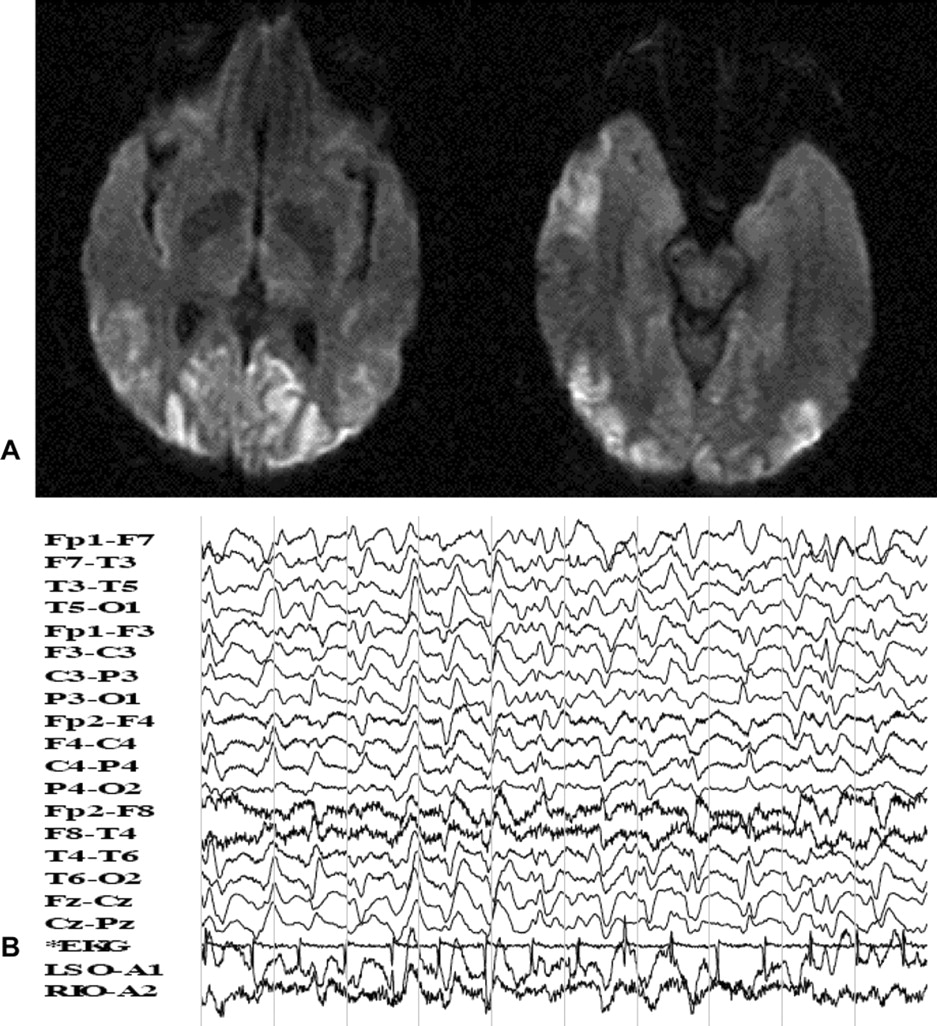

一位51岁女性因快速进行性记忆丧失、语言障碍和困难进行例行的日常活动。在入学之前,她在精神病院,因为视觉幻觉和异常行为。她患失语症,皮质盲和痉挛性夸张的反应,双边巴宾斯基,和频繁的多焦点的肌肉阵挛性抽搐。CSF 14-3-3蛋白升高。病人死后4个月的进展。这个病人可能的零星的克雅氏病(CJD), Heidenhain变体。1视觉障碍和迅速发展的主要症状被称为“Heidenhain变体”自1954年以来,库贾氏症。它展示了最为明显neuropathologic /放射枕叶的变化(图)。